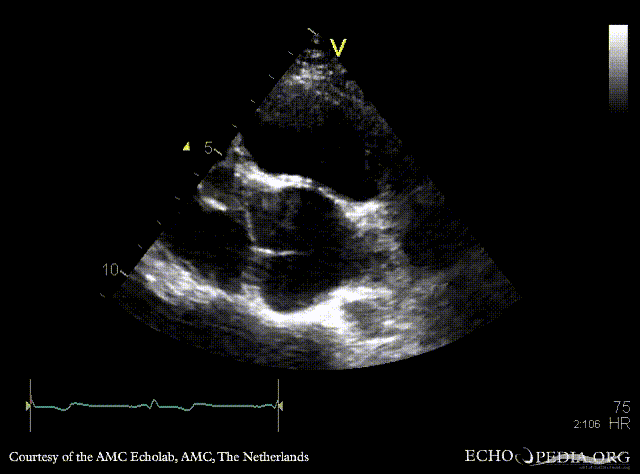

| Marfan Syndrome

| Courtesy of: AMC Echolab, AMC, The Netherlands

| A3CH

| A4CH with Color Doppler: mild mitral regurgitation